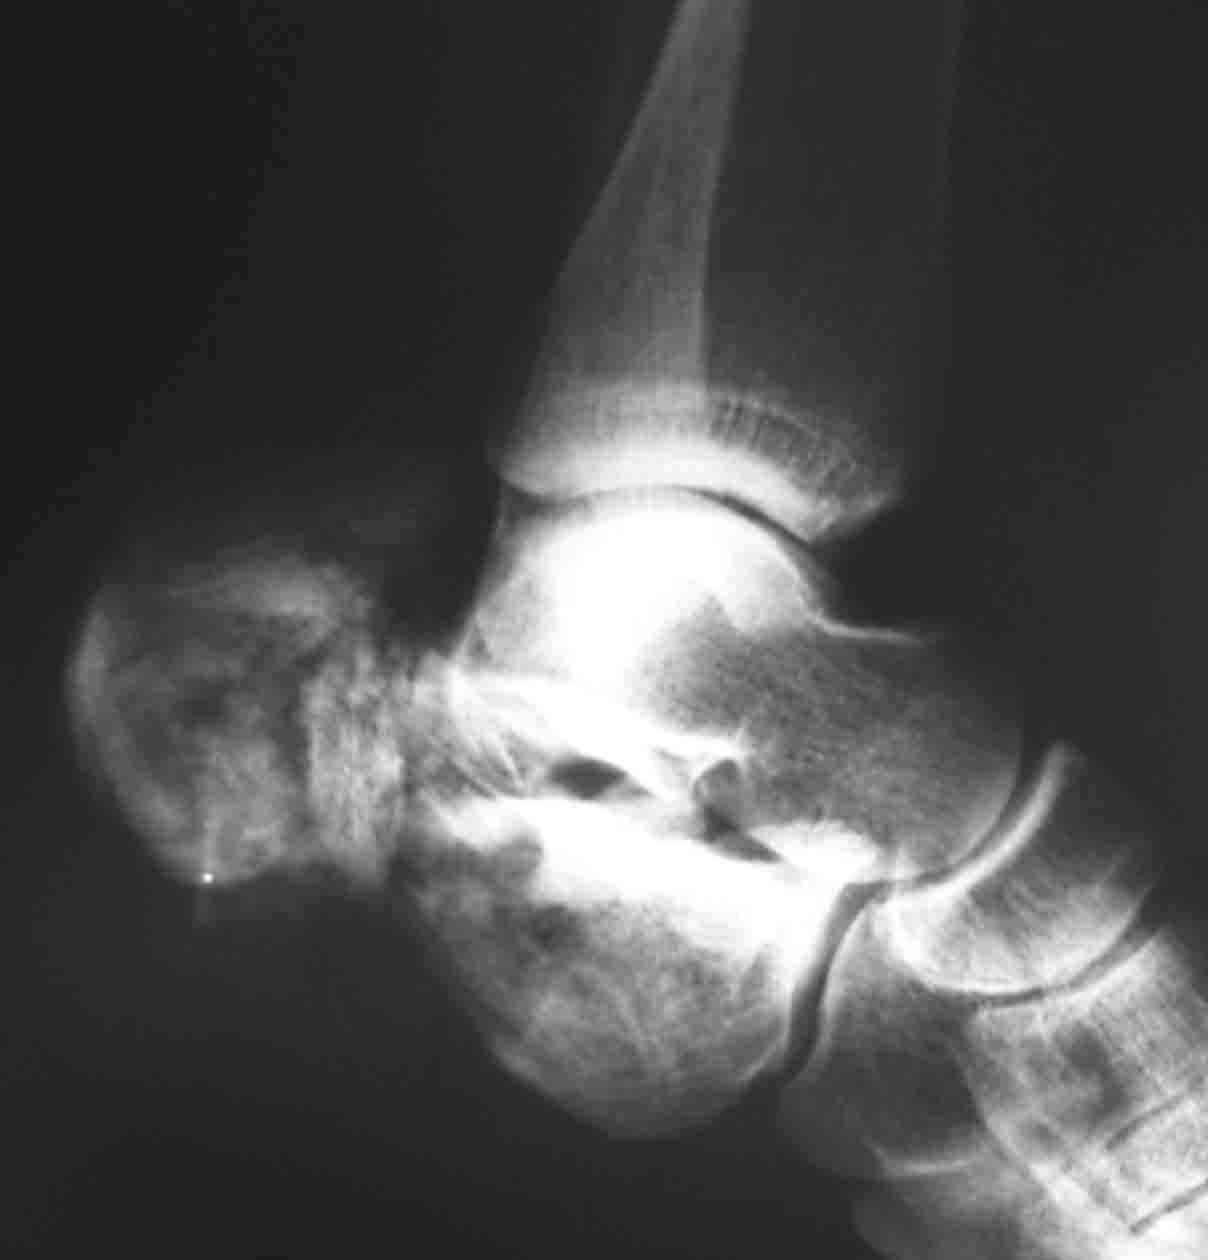

Пациентка 26 лет поступила в больницу 9 дней назад после кататравмы (падение с 4-го

этажа)Тяжелая сочетанная травма: Ушиб головного мозга средней тяжести.З/полифокальный

перелом таза (оскольчатый чрезвертлужный справа, латеральной массы крестца слева со

смещением отломков. З/оскольчатый перелом н/3 правого бедра. З/оскольчатый перелом

правой пяточной кости. Тупая травма живота - разрыв слизистой толст кишечника, кисты

яичника.